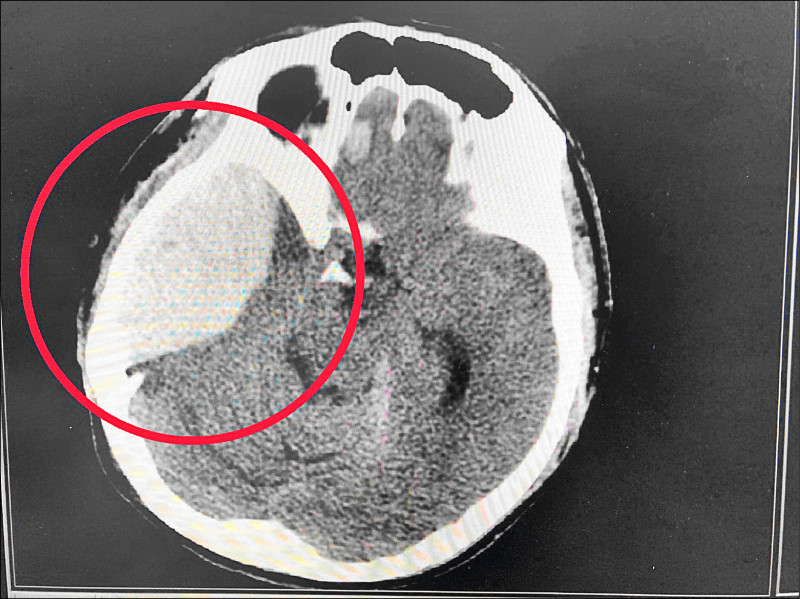

詎料隔天早上叫不醒,還失禁、左側肢體抽搐,送醫已意識昏迷,昏迷指數6分,右眼瞳孔放大,經檢查是顱骨骨折、右側硬腦膜上出血及急性硬腦膜下出血,合併腦幹壓迫。

南投醫院神經外科醫師蔡佳勳指出,患者腦部血塊厚度將近4公分,明顯壓迫腦幹,造成意識昏迷,經開顱手術清除血塊,減輕顱內壓,術後2週便出院,現已正常上班生活,還能彈吉他,歷經嚴重意外,患者也決心戒酒,提醒有外傷導致急性病徵,就應儘速治療。